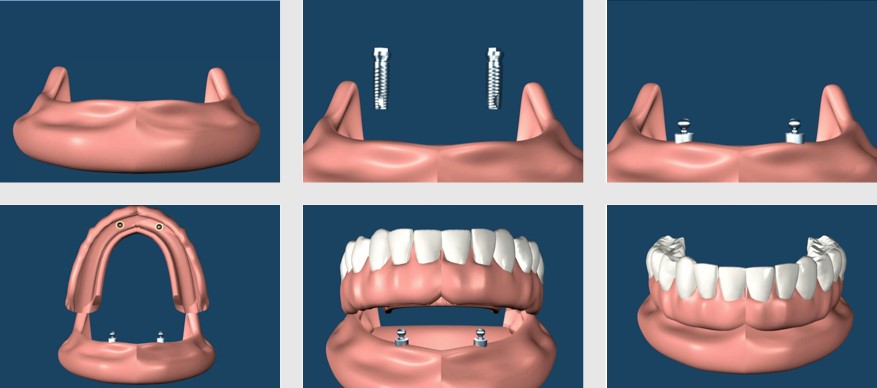

An implant-supported denture is used when a person doesn't have any teeth in the jaw, but has enough bone in the jaw to support implants. An implant-supported denture has special attachments that snap onto attachments on the implants.

Implant-supported dentures usually are made for the lower jaw because regular dentures tend to be less stable there. Usually, a regular denture made to fit an upper jaw is quite stable on its own and doesn't need the extra support offered by implants. However, you can receive an implant-supported denture in either the upper or lower jaw.